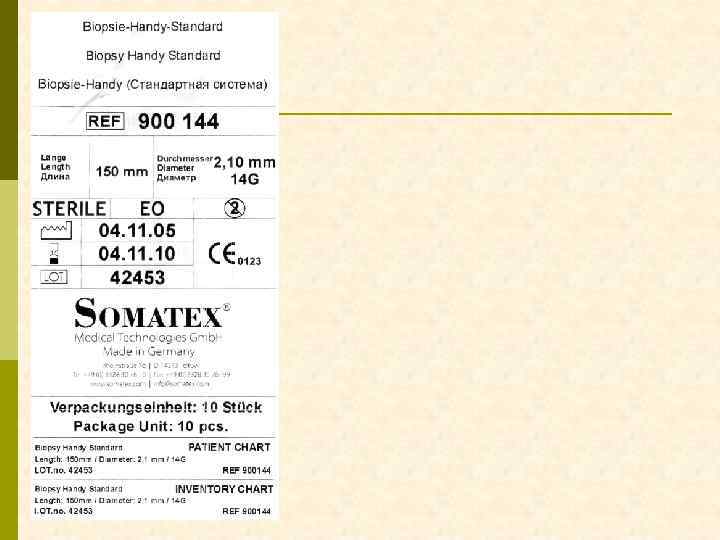

ЧТО НУЖНО ДЛЯ ВЫПОЛНЕНИЯ ДИАГНОСТИЧЕСКОЙ НЕФРОБИОПСИИ? Биопсионная игла Vim-Silverman’a игла Tru-Cut игла с пружиной Аппарат ультразвуковой диагностики (с ультразвуковой поддержкой нефробиопсия выполняется быстрее, но частоту осложнений она не уменьшает) А также: шприц 10– 20 мл, игла для п/к введения анестетик (новокаин 0, 5% 20– 40 мл) игла инъекционная 100– 120 мм скальпель предметное стекло консерванты для биоптата (N 3 !!)

АВТОМАТИЧЕСКАЯ (С ПРУЖИНОЙ) БИОПСИОННАЯ ИГЛА Meditech

АВТОМАТИЧЕСКАЯ (С ПРУЖИНОЙ) БИОПСИОННАЯ ИГЛА Monopty

Monopty